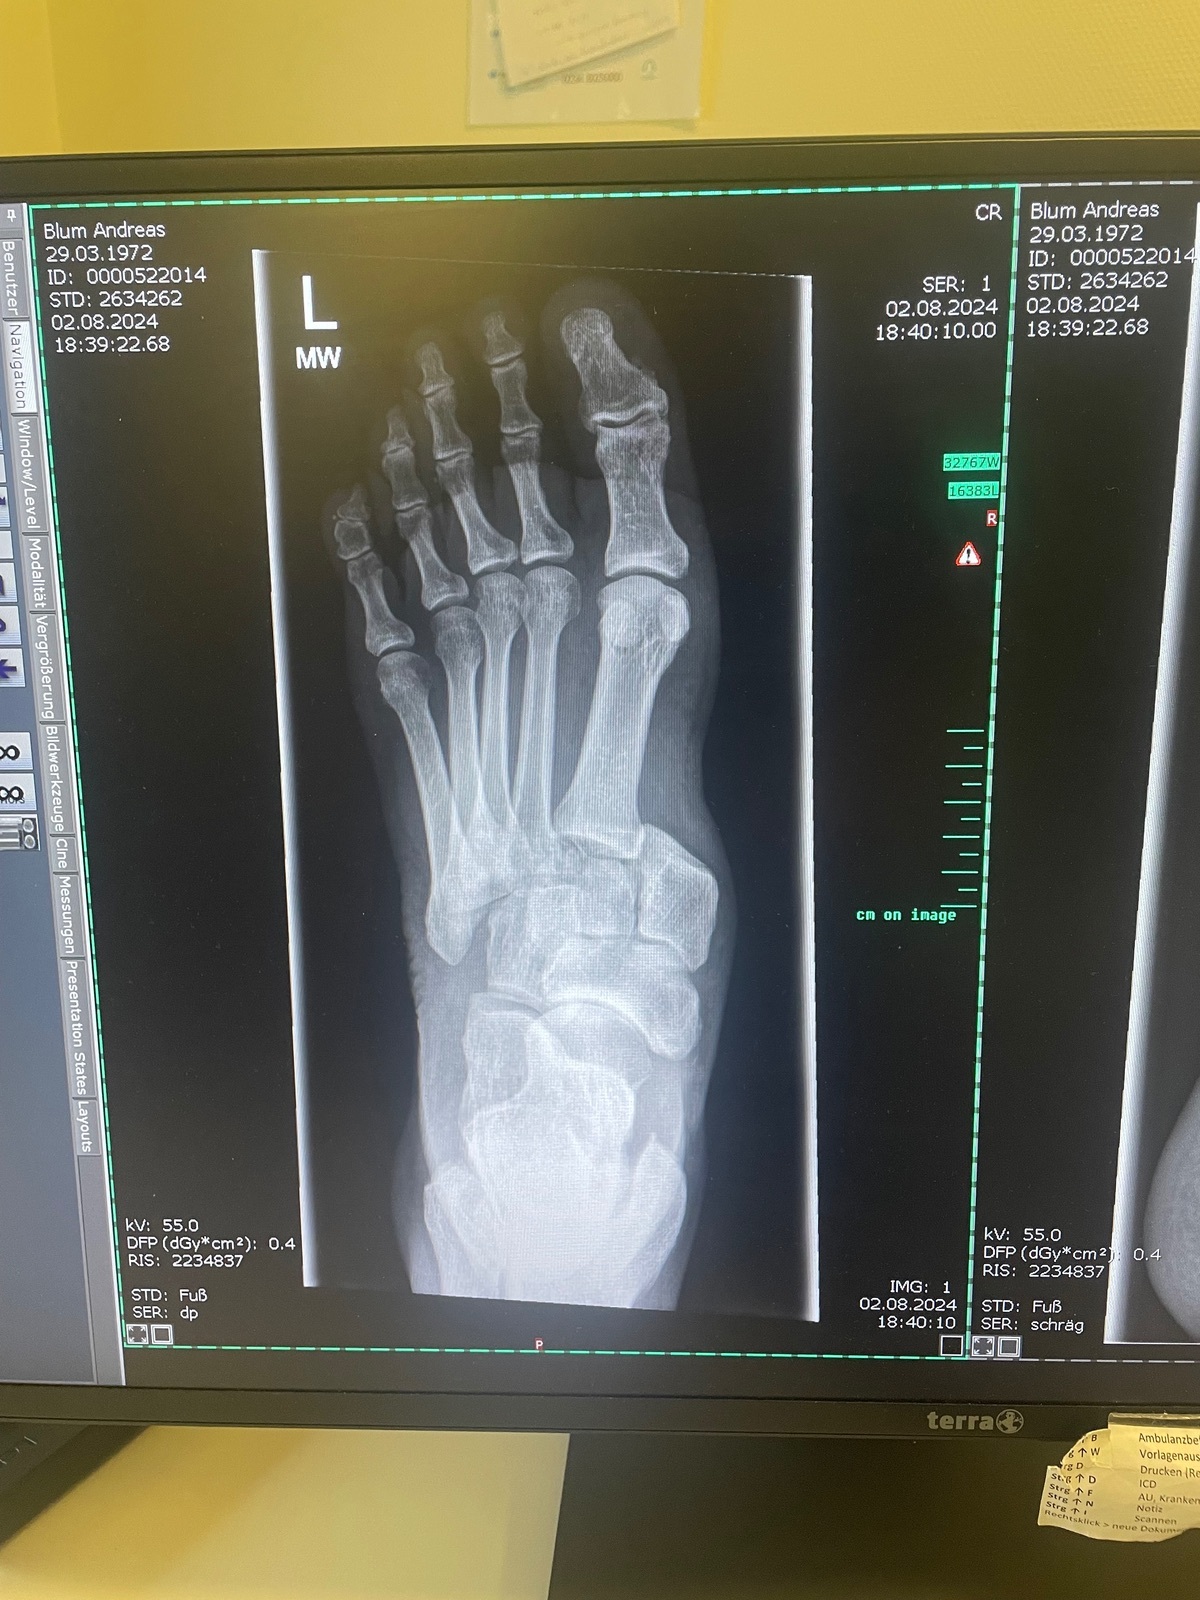

… dann das:

Offensichtlich traf meine Fußraste oder ein anderes hervorstehendes Teil meinen Vorderfuß und klemmte den ein. Die Folge: alle Mittelfußknochen wurden aus der Position gedrückt und etwa „eine Zehe“ weiter nach links verschoben.